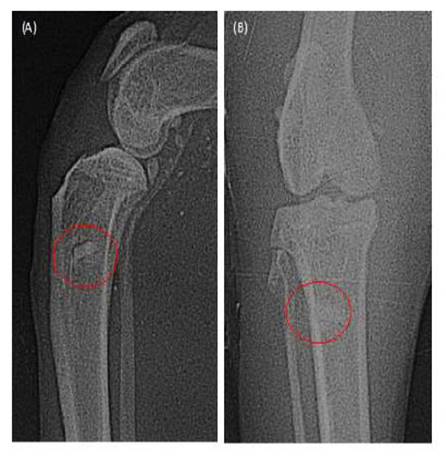

En la imagen radiográfica del posoperatorio inmediato del paciente canino (Figura 7) se visualiza una estructura radio-paca correspondiente al perfil completo del tornillo, donde no hay fractura o daño dentro de su estructura. En la imagen radiográfica del posoperatorio inmediato del paciente felino (Figura 8) se puede observar, de manera similar, que las imágenes radiopacas que corresponden a la tibia y al implante se visualiza completamente delimitado, sin fractura o daño dentro de su estructura. Así mismo, alrededor del implante se visualiza un halo radiolúcido, lo que diferencia el hueso del paciente con el implante insertado y corresponde a la inexistencia de osteointegración, la cual debe ocurrir en los meses posteriores a la cirugía.

Figura 8 Tornillo de hueso bovino liofilizado insertado en paciente felino sometido a cirugía de reparación extraarticular de ruptura de ligamento cruzado anterior. Radiografía tomada inmediatamente después de la cirugía, A) Vista frontal, B) Vista lateral